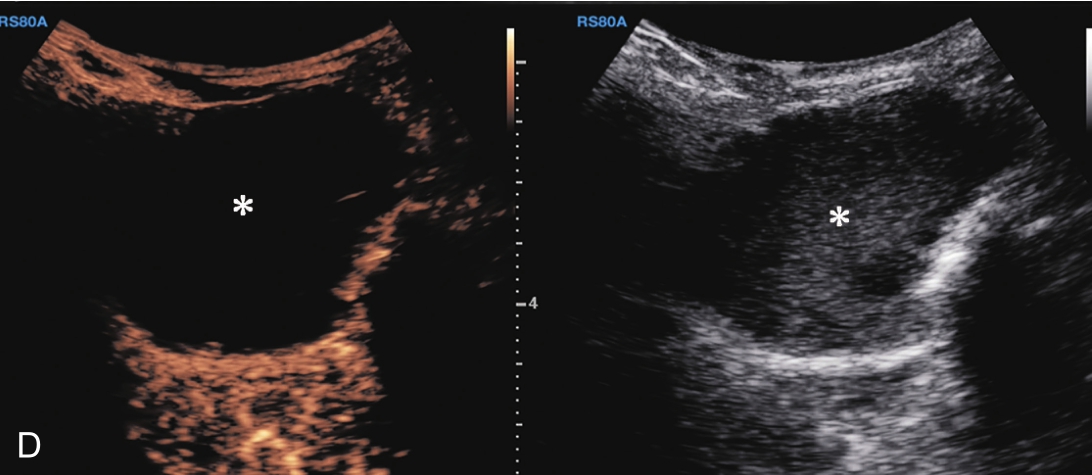

▲ 图 2-1-12(续)

C.彩色多普勒显示囊性团块(星号)内无血流信号;D.超声造影显示囊性团块内呈无增强;E.冈上肌腱完全断裂,关节腔积血(星号);F.超声引导下穿刺液体抽吸及药物注射治疗,箭头示穿刺针